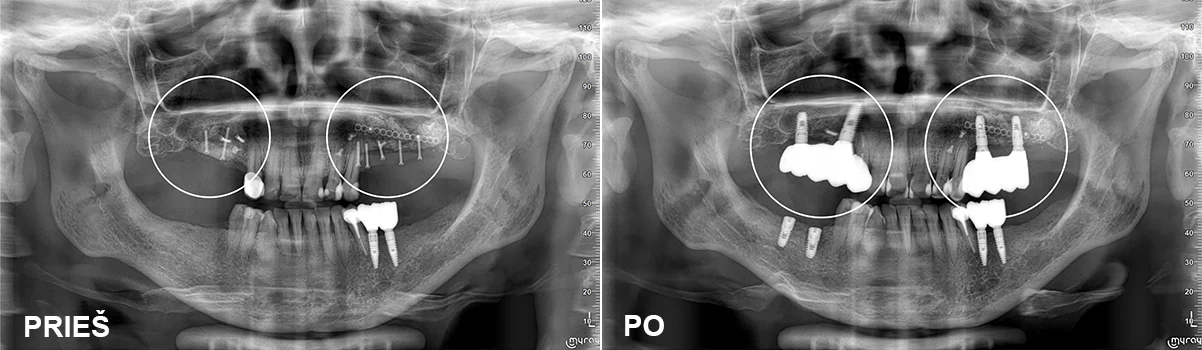

All on 6

Visi paciento dantys buvo stipriai pažeisti periodontito, klibėjo, dantenos kraujavo, jų išsaugoti nebuvo įmanoma, todėl dantys pašalinti. Viršutiniame žandikaulyje atlikti sinuso pakėlimai įsriegti šeši implantai viršuje ir šeši apačioje. Implantai po operacijos protezuoti laikinais protezais. Po šešių mėnesių pagaminti nuolatiniai cirkonio oksido dantys su titano sija.

Protezavimas – gyd. Kristina Gegeckaitė

Klinika „Ortodenta“